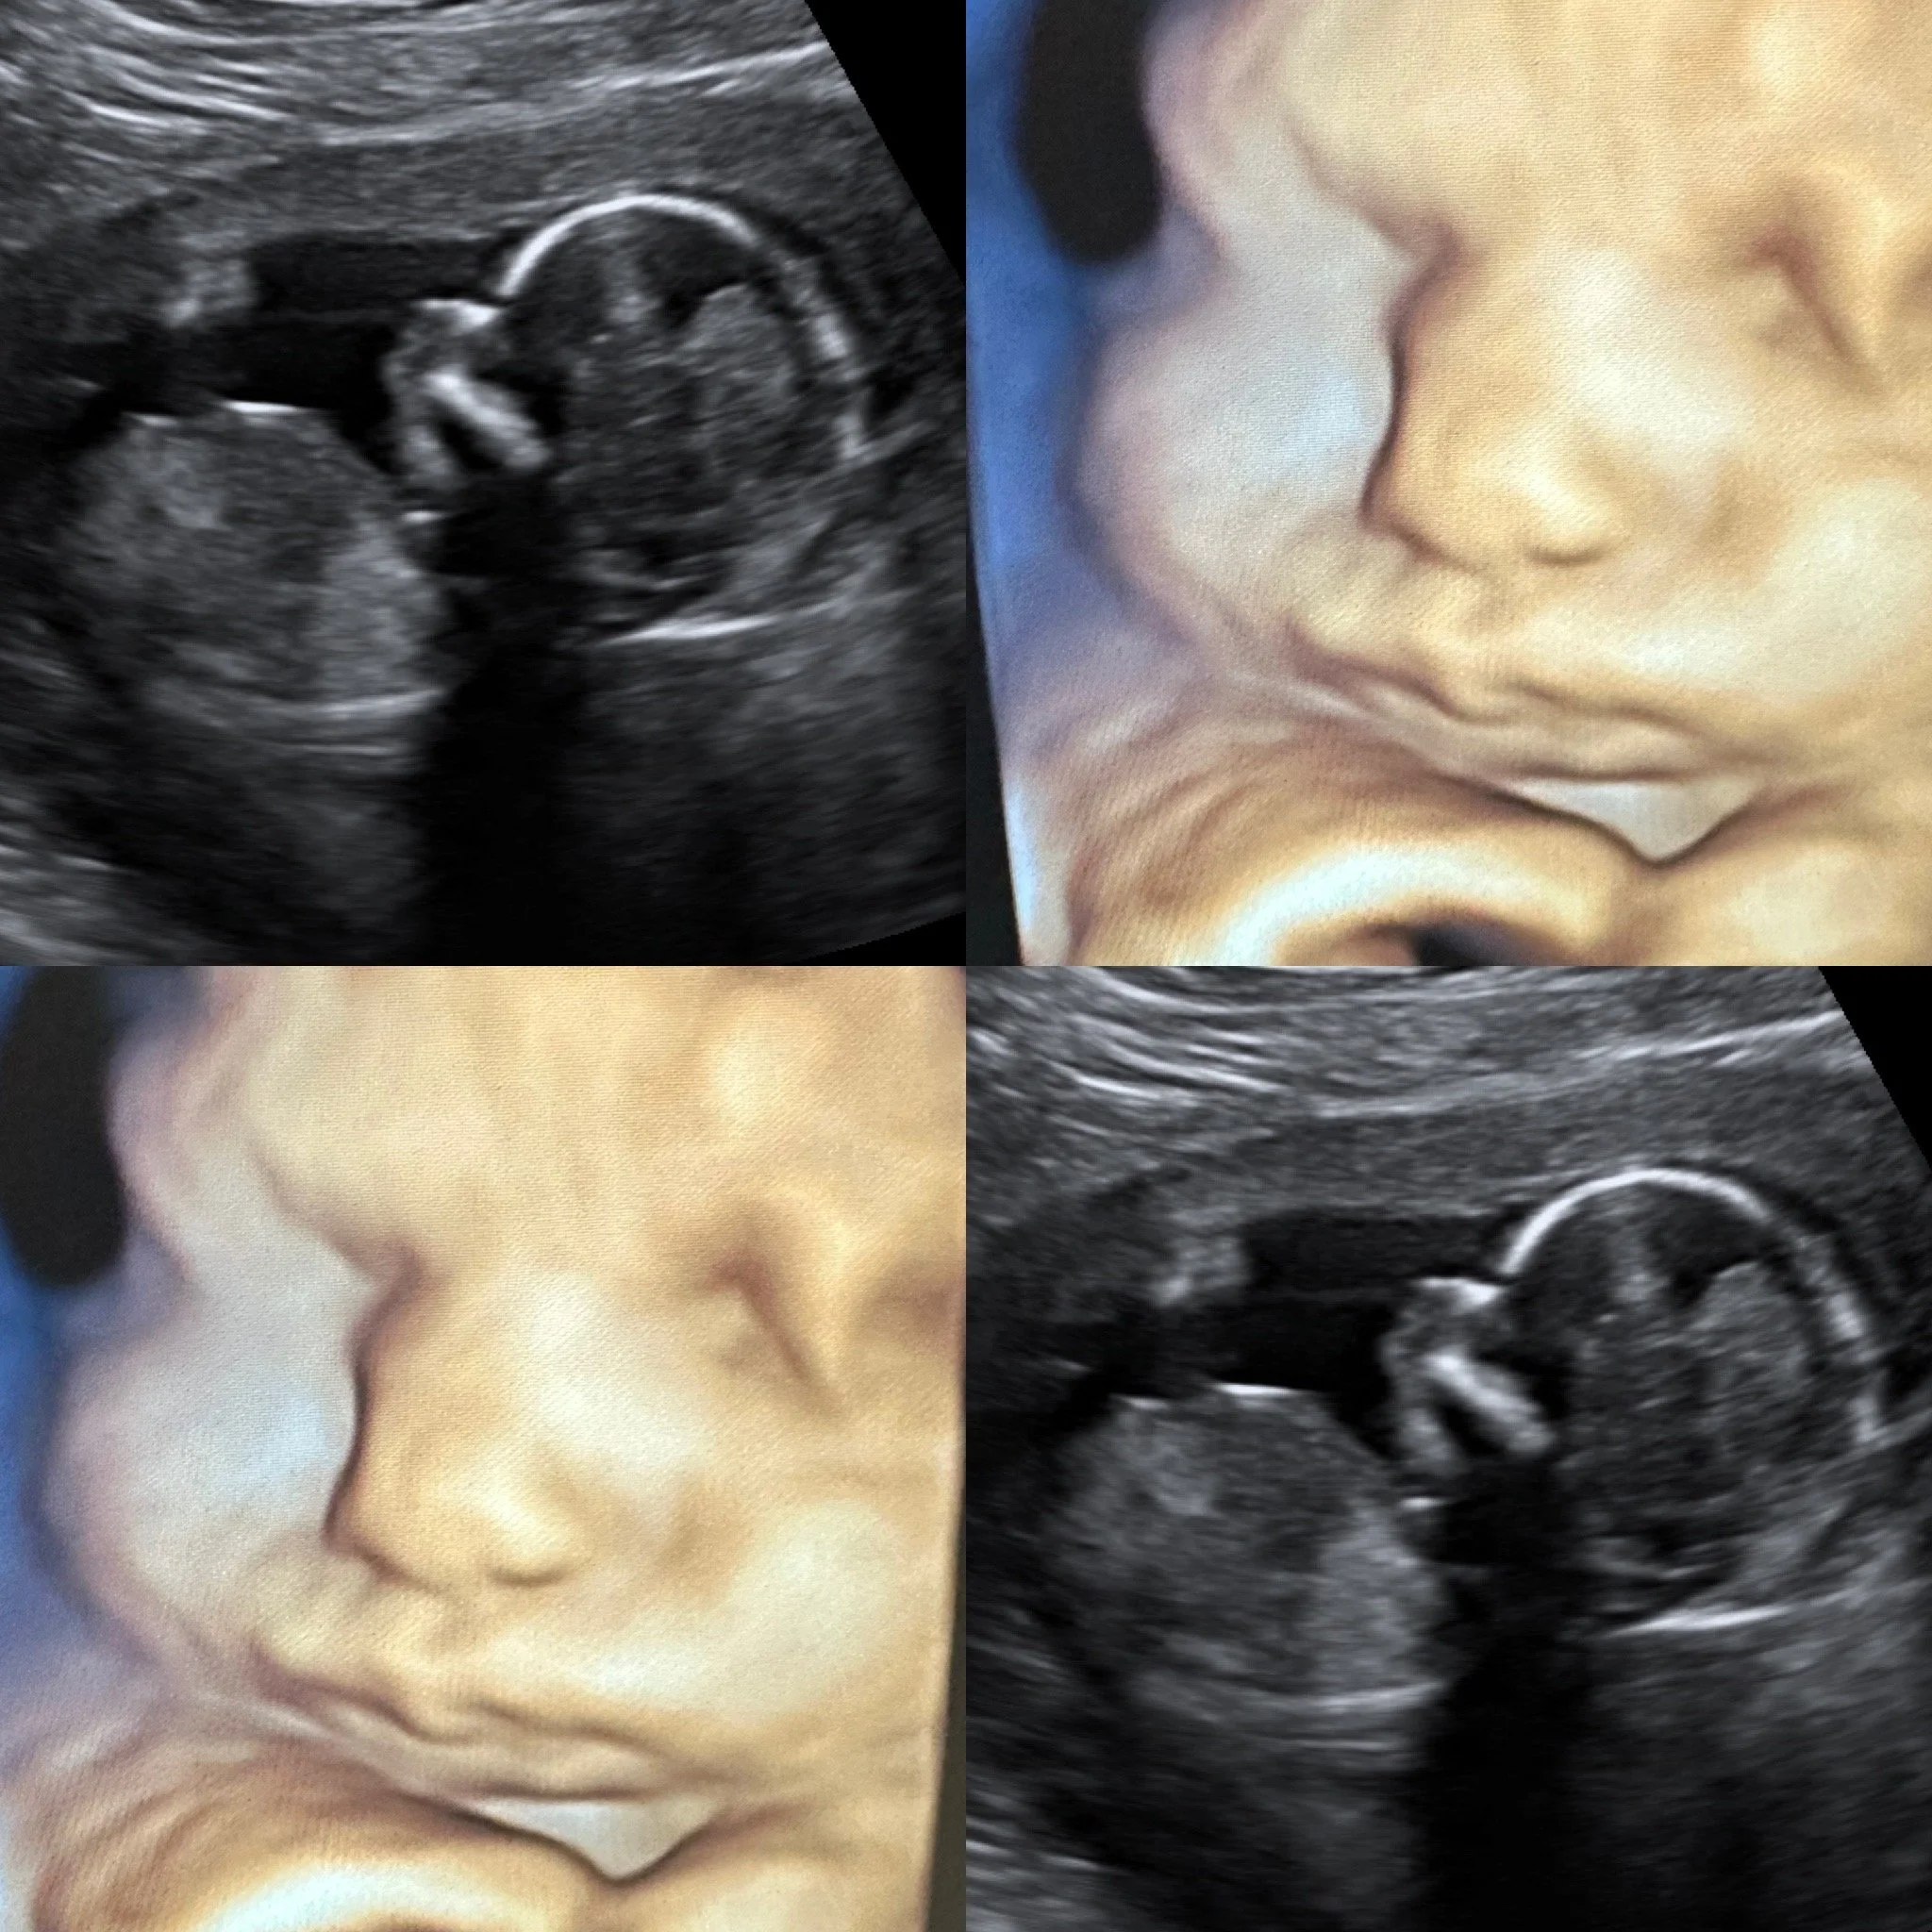

Confirm Your Baby's Gender Bloodwork With Us!

Did you have genetic bloodwork done & now you want to confirm your baby's gender with an ultrasound? So many people do! Come see us 6 days a week!